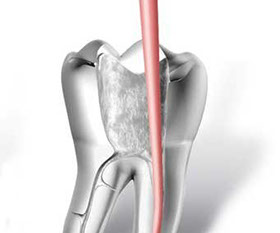

• accesso alla camera pulpare mediante frese diamantate

• asportazione della polpa e sagomatura dello spazio endodontico con strumenti meccanici (in nichel-titanio), con l'ausilio della detersione del canale radicolare (acqua ossigenata, ipoclorito di Sodio, calcio-chelanti)

• otturazione di tutto l'endodonto mediante materiali termoplastici (guttaperca) e cementi biocompatibili